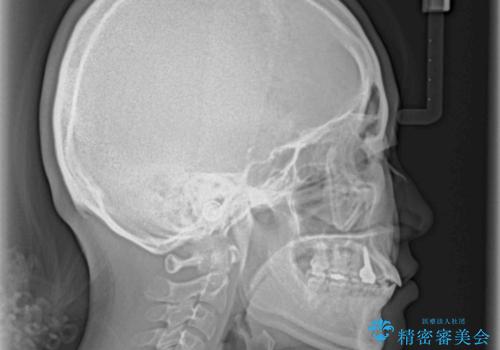

- 歯の欠損による隙間だらけの歯並びを気にして来院された患者様です。

上顎左右1本ずつ欠損していたため、歯列矯正により欠損部位にスペースを集め、その後欠損部位をインプラントにて補綴することとしました。

インビザラインによる矯正治療も提案しましたが、長時間の装着や自己管理が難しいとお考えで、ワイヤーによる矯正治療を行いました。

歯並びは比較的早めに整いましたが、インプラントを埋入するにあたって前後の歯根位置を改善する必要があり、矯正治療に期間を要することとなりました。